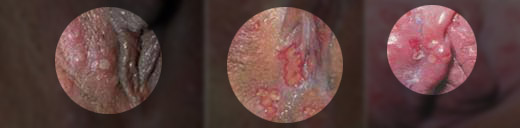

阴部溃疡、糜烂、化脓症状图

专家指出:不洁性生活是导致性传播疾病的首要因素,在临床诊疗中女性阴部出现溃烂、溃疡、糜烂等症状,75%是生殖器疱疹所致,15%属于尖锐湿疣,10%是梅毒。如果溃烂症状不加遏制,即使只有一丝病菌残留,也会随时复制扩散,导致症状反复。

主要症状:生殖器疱疹感染后平均约3~5日,女性患病处先有灼热感,随即发生红肿并出现红斑,撑大直至破溃而形成糜烂或浅的溃疡,还会化脓发臭,患者自觉疼痛。